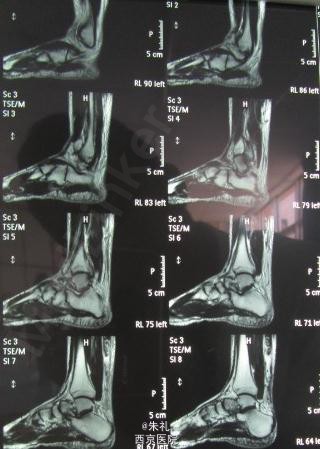

患者中年男性,因行走时拉伤致左下肢肿痛、活动障碍1月余,曾到当地性“消炎针输液”、当地行长期中草药外敷等治疗但效果不理想,到我院就诊,确诊为陈旧性跟腱断裂。

入院查体:左踝关节明显水肿,跟腱区可扪及一明显凹陷及空虚感,跟腱连续性中断,跖屈乏力 提踵试验(+),Thompson征(+),Matles试验(+)

Abraham V-Y加上Bosworth法对陈旧性跟腱断裂并缺损进行治疗